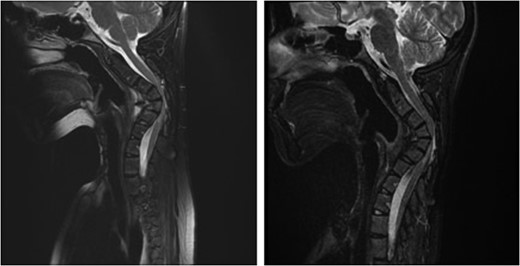

Sagittal magnetic resonance image 3 years after the second surgery, showing small soft tissue enhancement, suggesting a possible residual tumor, which remained unchanged with follow-up.